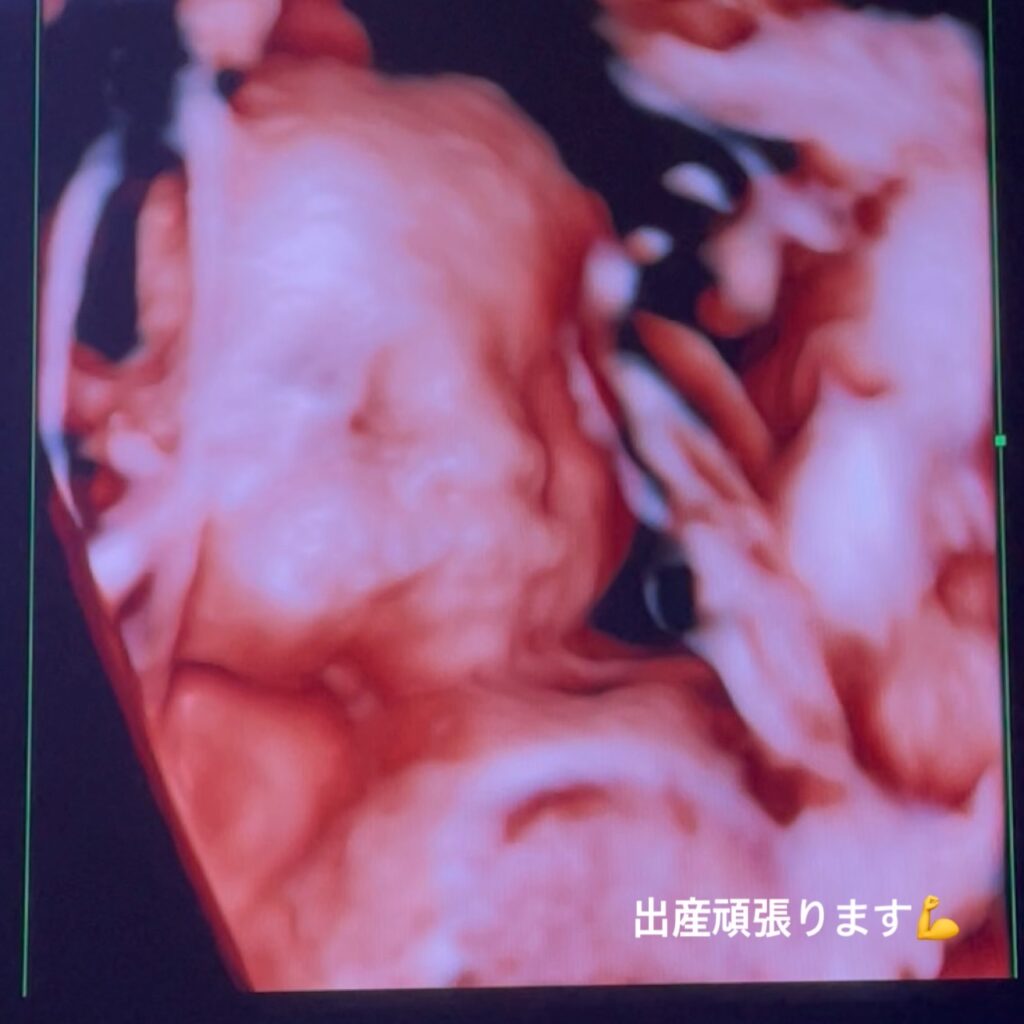

そして、私事にはなりますが、ご報告です!

現在、妊娠9ヶ月目で今月より産休に入ることになりました。

予定日は11月下旬で、色々と不安や心配事はありますが、元気な赤ちゃんを産めるよう頑張りたいと思います!